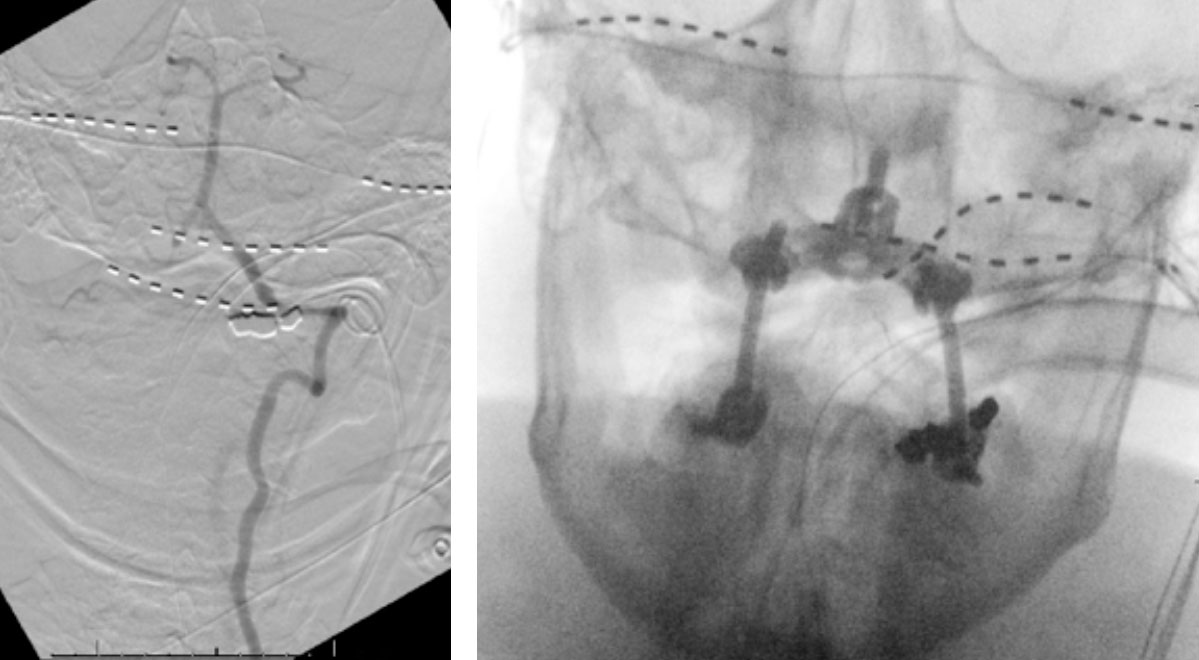

On rotation to the left, the patient experienced mild symptoms, however no significant Vertebral Artery or basilar reduction in flow was observed. On rotation to the right, the patient experiences slightly more moderate symptoms, however no significant Vertebral Artery or vascular reduction flow was observed. On hyper extension of approximately 10-15 degrees, passively performed by the patient until symptoms are reproduced, angiogram demonstrates complete occlusion of the right Vertebral Artery at approximately the C2-C1 level. (Figure 5)

Intraoperative angiography was then repeated again, showing good flow through the right Vertebral Artery into the Basilar Artery. Intraoperative fluoroscopy was then also performed to confirm good position of the screws and rods in both AP and lateral projections. (Figure 7)